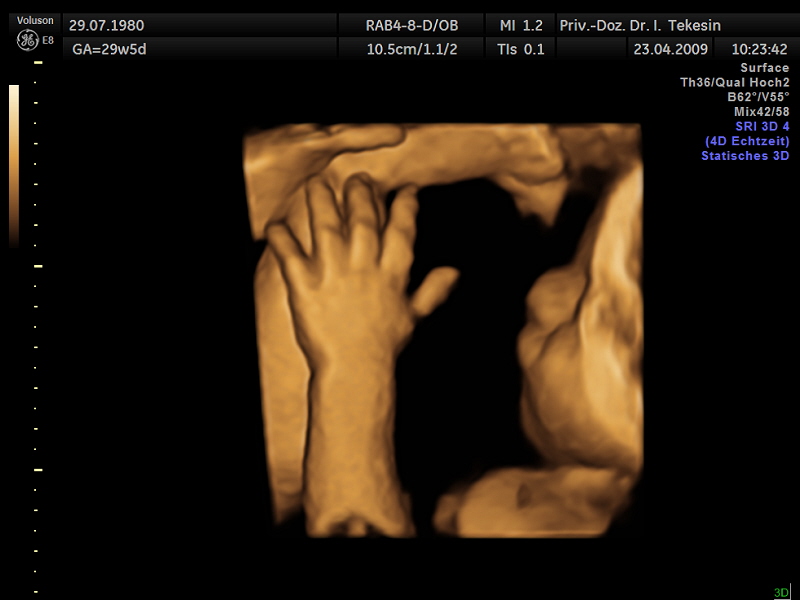

Fünf Finger

Fünf Finger (3D-Darstellung)